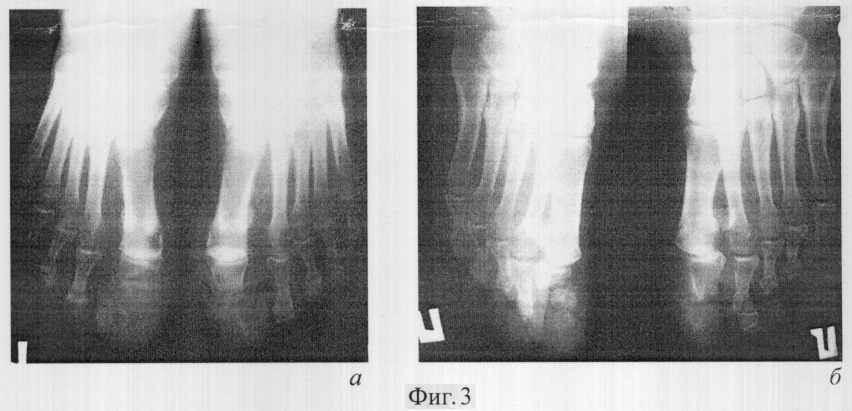

Выполняется рентгенография костей таза (от 22.02.2006), на основании которой заподозрены локальные деструктивно-литические изменения в области передней наружной ости крыла правой подвздошной кости (фигура 1а).

На серии КТ-грамм костей таза (от 27.02.06) определяется деструкция крыла правой подвздошной кости с замещением костной ткани мягкотканным компонентом, выходящим за ее пределы (фигура 1б).

Трехфазная сцинтиграфия (от 9.03.06): в области рентгенологически выявленных изменений наблюдается повышенная аккумуляция РФП высокой интенсивности в фазу радионуклидной ангиографии, мягкотканную и костную фазы (фигура 1в, г). Однако однозначного заключения о природе патологического очага по результатам трехфазной сцинтиграфии сделать нельзя.